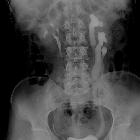

Circumcaval

ureter - Congenital vascular cause of obstructive hydronephrosis. 25-year-old male patient with right circumcaval ureter showing medial deviation of the right ureter at L3 level with hydroureteronephrosis with a ‘reverse J’ configuration.